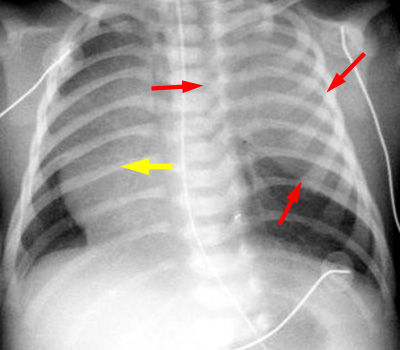

Initial postnatal CXR demonstrates a solid appearing mass in the left upper chest (red arrows) with mass effect and shift of the mediastinum (yellow arrow). At this point, the CLE is filled with fluid and thus mimics a solid mass.